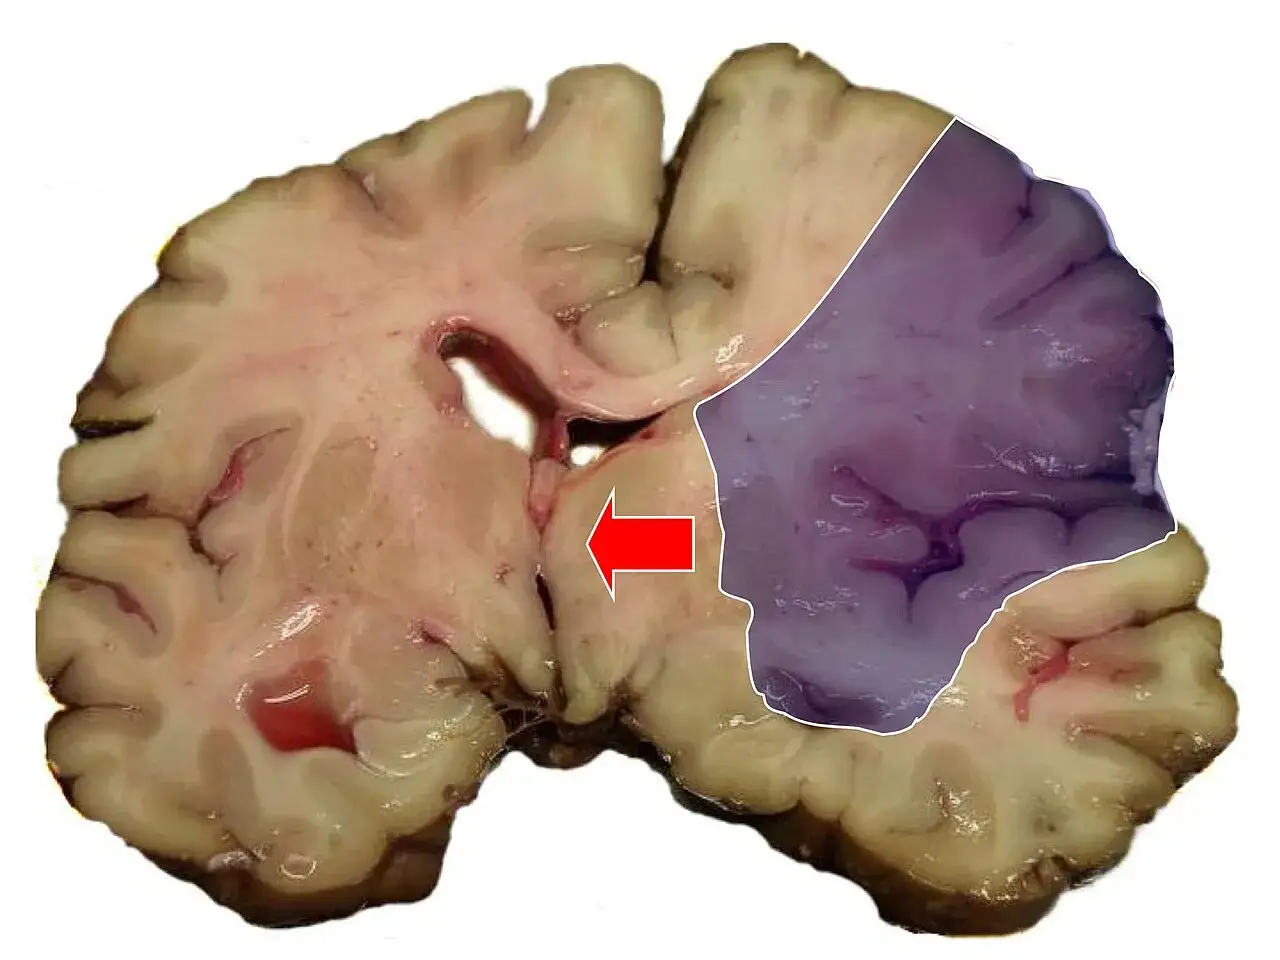

Udar krwotoczny, czyli wylew gdy naczynie pęka pod ciśnieniem

Udar krwotoczny, znany również jako wylew, jest mniej powszechny, ale często bardziej dramatyczny w przebiegu. W tym przypadku dochodzi do pęknięcia ściany naczynia krwionośnego w mózgu, co prowadzi do wylewu krwi do tkanki mózgowej. Krew ta, gromadząc się, uciska na struktury mózgu i uszkadza je. Główną i najczęstszą przyczyną udarów krwotocznych jest niekontrolowane, długotrwałe nadciśnienie tętnicze. Wysokie ciśnienie krwi osłabia ściany tętnic, czyniąc je bardziej podatnymi na pęknięcia. Inne możliwe przyczyny to pęknięcie wrodzonych tętniaków (czyli uwypukleń ściany naczynia) lub malformacji naczyniowych, które są nieprawidłowymi połączeniami naczyń krwionośnych.Główne choroby prowadzące do udaru poznaj cichych sprawców katastrofy

Jeśli miałbym wskazać jednego winowajcę, który jest odpowiedzialny za największą liczbę udarów, byłoby to bez wątpienia nadciśnienie tętnicze. To najważniejszy i najczęstszy czynnik ryzyka zarówno udaru niedokrwiennego, jak i krwotocznego. Wysokie ciśnienie krwi, utrzymujące się przez długi czas, działa jak młot na nasze naczynia krwionośne. Uszkadza ich delikatne ściany, czyniąc je sztywnymi i mniej elastycznymi. Takie uszkodzone naczynia są znacznie bardziej podatne na pęknięcia (co prowadzi do udaru krwotocznego) lub na tworzenie się w nich blaszek miażdżycowych i zakrzepów (co sprzyja udarowi niedokrwiennemu).